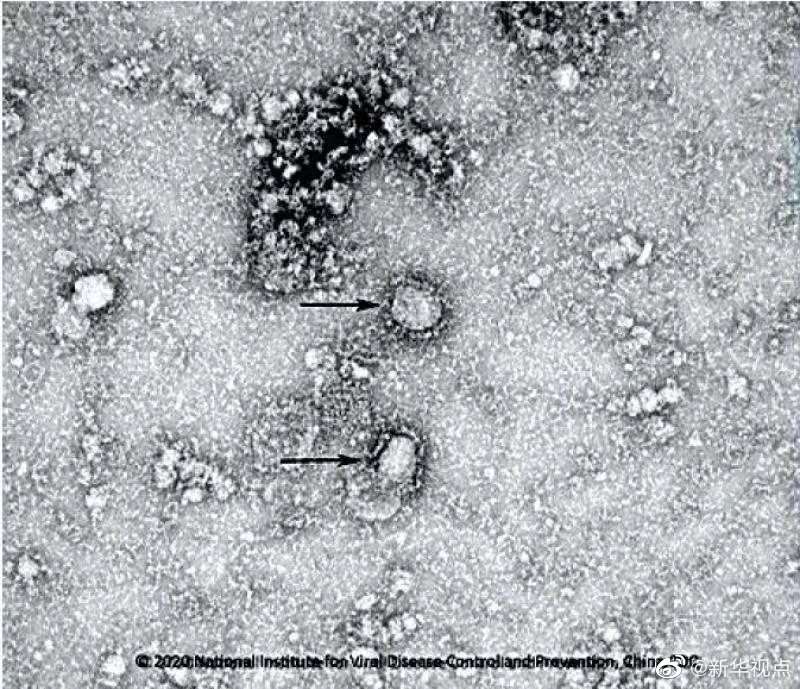

國家病原微生物資源庫于2020年1月24日發(fā)布了由中國疾病預(yù)防控制中心病毒病預(yù)防控制所成功分離的我國第一株病毒毒種信息及其電鏡照片、新型冠狀病毒核酸檢測引物和探針序列等國內(nèi)首次發(fā)布的重要權(quán)威信息,并提供共享服務(wù)??床《尽罢嫒荨薄ㄓ浾咛飼院健⑼醣枺?/p>

好消息!中國疾控中心成功分離我國首株新型冠狀病毒毒種,它長這樣!-新華網(wǎng)